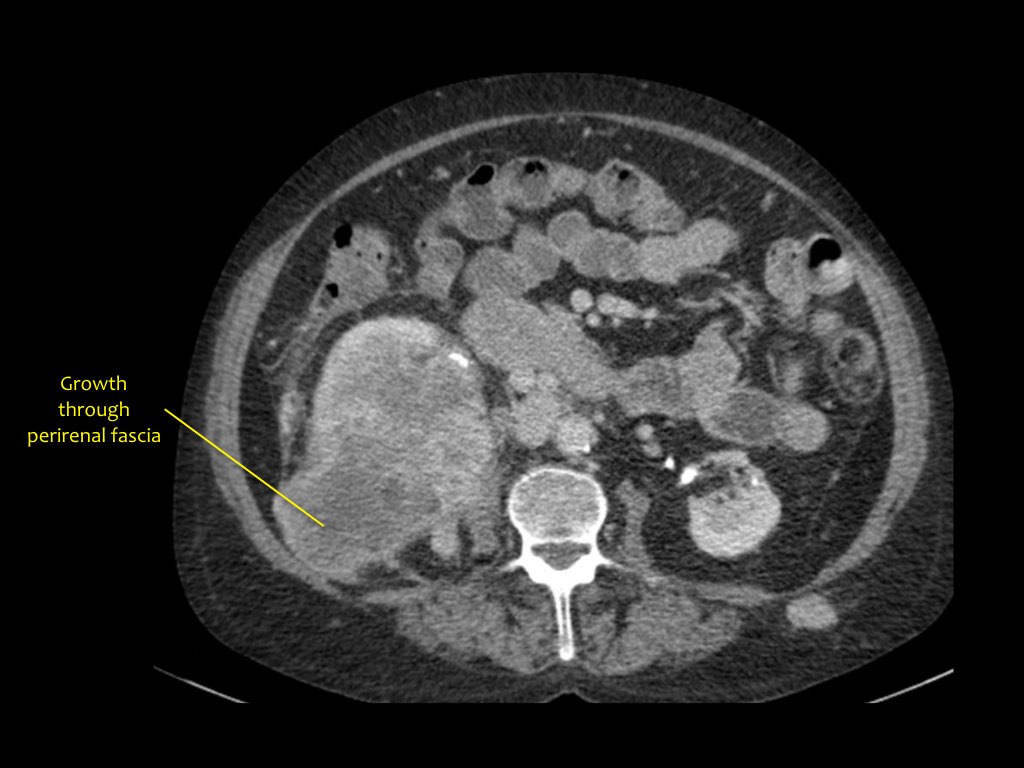

Phân giai đoạn RCC

RCC có thể xâm lấn mỡ quanh thận vượt qua cân thận và có thể lan vào tĩnh mạch thận, tĩnh mạch chủ dưới (IVC) hoặc tuyến thượng thận cùng bên.

Đối với phẫu thuật viên, điều quan trọng là cần biết có huyết khối u trong IVC hay không và liệu huyết khối có lan vào lồng ngực trên cơ hoành hay không (cần có phẫu thuật viên lồng ngực trong ca mổ).

Khoảng 25% bệnh nhân đã có di căn tại thời điểm chẩn đoán.